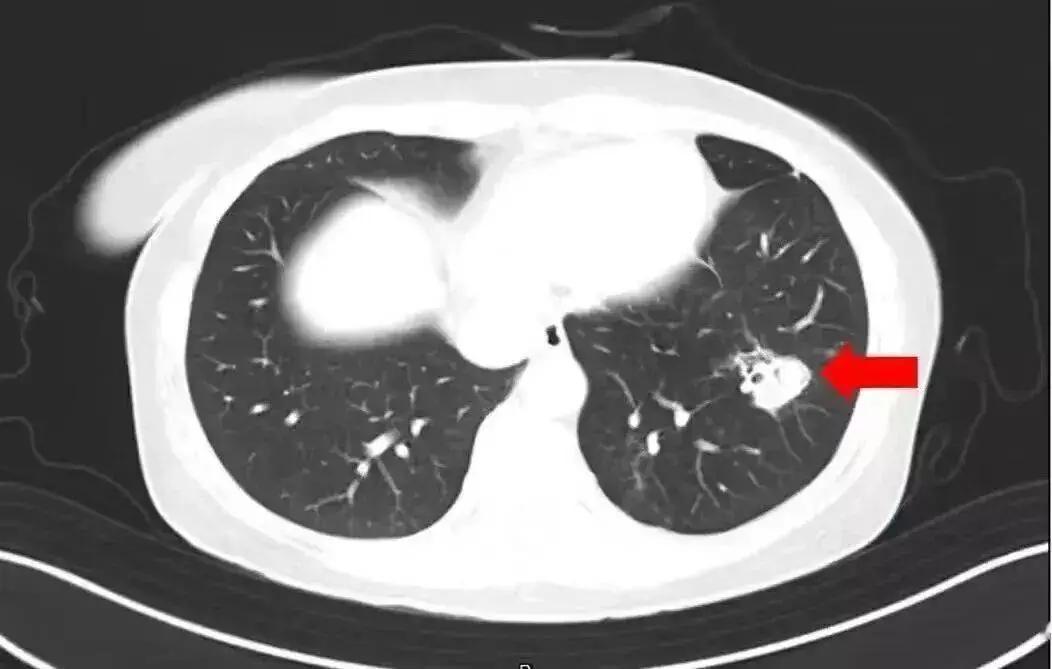

太吓人!家里这东西是Ⅰ类致癌物,6岁娃脑子被“啃”出十几个洞! 谁能想到,天天待的家里竟藏着致命致癌物!河南6岁女童持续发烧17天,意识不清送医后,医生发现她脑子被“啃”出十几个洞,再晚几天就可能被“啃空”,罪魁祸首竟是霉菌! 这可不是个案!杭州女子清发霉衣柜没戴口罩,高烧40℃确诊曲霉菌感染;扬州大爷大扫除吸入霉菌孢子,诱发肺曲霉病差点出事。霉菌被世卫组织列为Ⅰ类致癌物,黄曲霉素毒性是砒霜68倍,藏在卫生间、洗衣机、冰箱密封条里,咱天天接触却浑然不觉! 咱中国人讲究居家安稳,可这看不见的霉菌正在偷偷害健康!免疫力低的老人、孩子最易中招,轻则过敏咳嗽,重则感染脏器甚至致癌。 你家卫生间、冰箱有没有霉斑?平时都怎么除霉?评论区分享你的实用妙招,帮大家远离这隐形杀手!黄曲霉素致癌 食品致癌物 冰箱致癌物